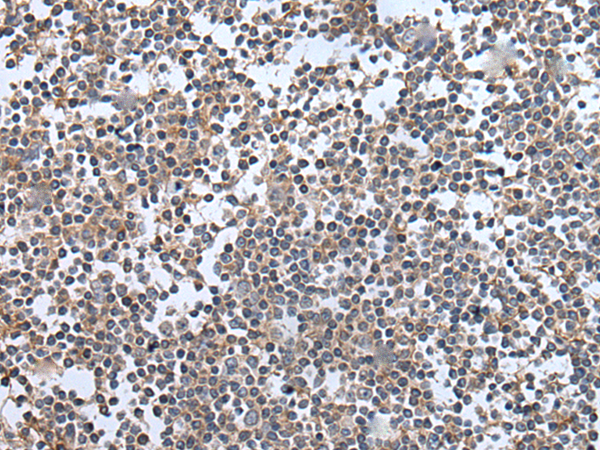

分类: 科研抗体货号: P12878别名: OOMD5; WEE1B应用: IHC反应种属: Human